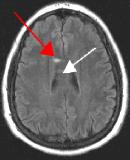

Fig. 2

By turning CSF dark, bright periventricular lesions such as MS plaques become much more conspicuous. Fig. 1 shows a typical T2-weighted axial image of the brain in which CSF in the ventricles appears bright. A lesion on the right is present (red arrow) that is also bright similar to CSF. Fig. 2 is a corresponding FLAIR image showing an obvious bright MS plaque (white arrow) against a background of dark CSF and gray parenchyma with additional more subtle lesions.